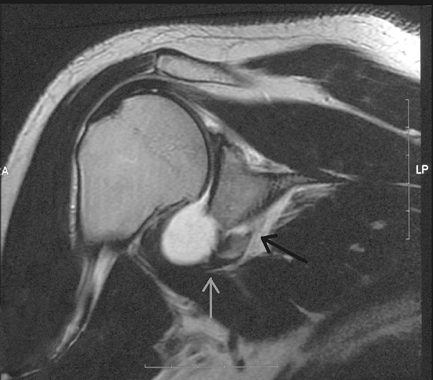

Figure 32-3 Anteroposterior radiograph demonstrating a bony Bankart injury (black arrow) and Hill-Sachs lesion (white arrow).

posterolateral margin comes into contact with the anterior glenoid rim.

fracture and bone loss is termed a Hill-Sachs lesion (Fig. 32-3).

It can occur in ≤80% of anterior dislocations and may be present in an

This arises when a portion of the anteroinferior rim of the glenoid is

dislocates anteriorly (Fig. 32-4). When the

fractured piece contains >20% to 25% of the glenoid surface area, it

Figure 32-4 Coronal plane MRI demonstrating fracture of the anteroinferior glenoid (black arrow) and maintenance of the labral attachment to the glenoid rim (gray arrow).